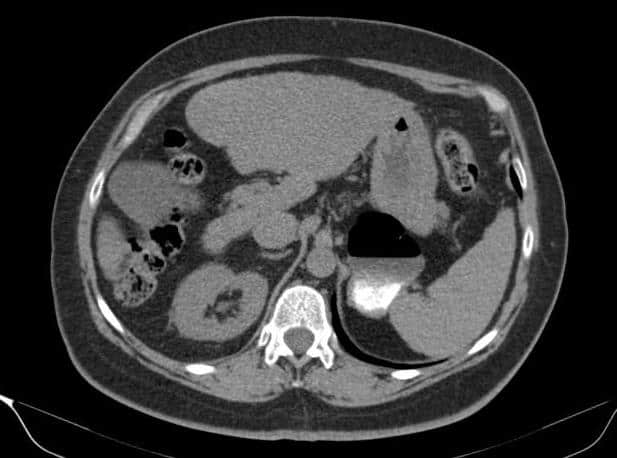

Túi thừa dạ dày - Ảnh 4

Túi thừa dạ dày

» Thông tin: Nữ giới – 54 tuổi.

» Lâm sàng: Kiểm tra sức khỏe.